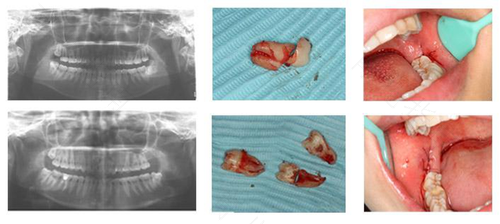

在牙齿出现病症后,很多人都会选择去医院拔牙,在拔牙之后,医生会开出一些抗菌消炎的药物,并且对拔牙部位放一个消毒棉球,以防止牙龈出血,在拔牙后回到家里睡一觉醒来,发现拔牙部位有血。拔牙后睡觉出血怎么办?